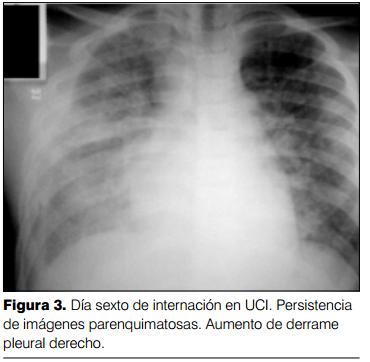

Persistió con fiebre durante la internación en la UCI, recibiendo antibióticos (penicilina cristalina y claritromicina) durante 8 días. Persistencia de imágenes parenquimatosas pulmonares durante los primeros días de internación con derrame pleural (figura 3). Ecocardiograma evidenció mínimo derrame pericárdico con FEVI normal. Al quinto día del ingreso se confirmó el diagnóstico de hantavirus: investigación de IgM e IgG específica para hantavirus, técnica de ELISA (FOCUS technologies): resultado positivo, realizado en Departamento de Laboratorio de Higiene Pública, Unidad de Virología, Ministerio de Salud Pública.